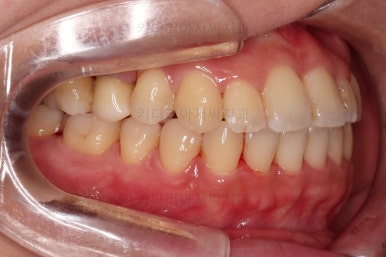

초진 시, 입안의 모습이에요.

결손부위가 눈에 띄고요.

결손부위가 양쪽에 있다보니 윗니 중간에 틈새가 벌어졌네요.

뒤쪽의 빈공간으로 치아들이 도미노처럼 쓰러져서 그렇습니다.

앞니의 약간의 틈새, 약간의 삐뚤어짐, 약간의 중앙선 틀어짐 등 심하진 않으나 약간씩의 문제점들이 있네요.